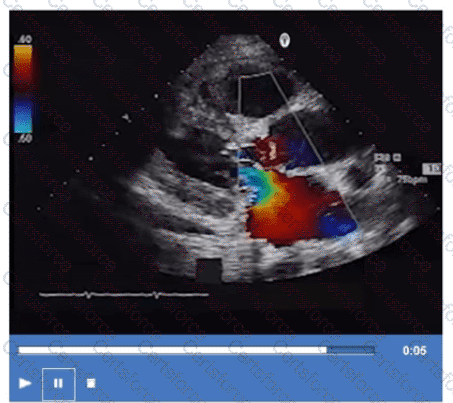

What is the direction of the mitral regurgitant jet in this video clip?